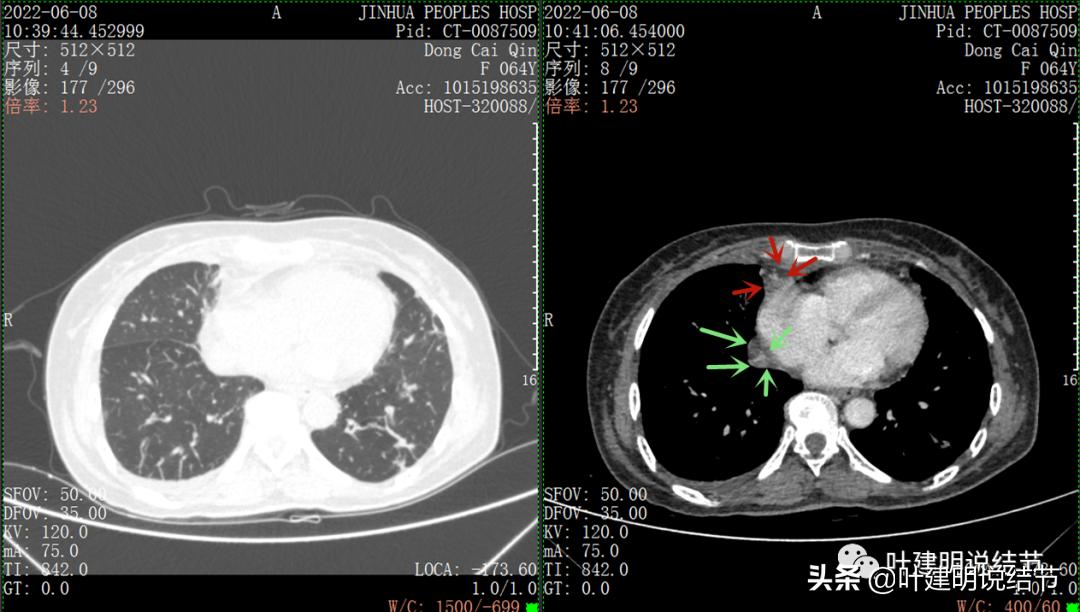

再来看看她的CT增强图像:

以下图片左侧是肺窗,右侧是纵隔窗。红色箭头示病灶,桔色箭头示无名静脉,黄色箭头示支气管,砖色箭头示上腔静脉,蓝色箭头示主动脉,紫色箭头示肺动脉。

绿色箭头示近膈面处,心脏边病灶

此灶与主病灶不是完全相连的

病灶占据前纵隔从上到下全程,多中心,密度不均,对心脏与大血管有压迫,没有明显侵犯

病灶表面不平,中间有坏死